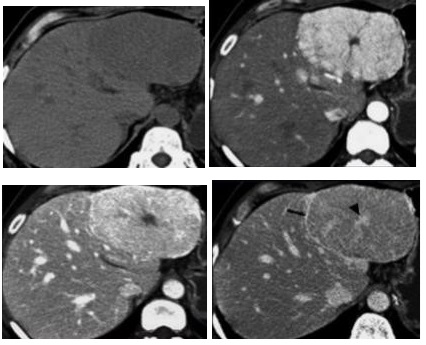

El principal factor de riesgo para su desarrollo es la cirrosis, principalmente la relacionada con la hepatitis viral crónica. Es este caso la hepatitis C, cirrosis alcohólica, cirrosis causada por hemocromatosis y cirrosis biliar primaria. La mayor parte de los casos en esta zona están relacionados con el virus de la hepatitis B, asociado o no con aflatoxina (micotoxinas producidas por dos especies de Aspergillus, un hongo localizado en especial en zonas con climas cálidos y húmedos). En el estudio de tomografía multicorte con técnica multifase el carcinoma hepatocelular (CHC) tiene vascularización predominantemente arterial, lo que determina un patrón de comportamiento específico caracterizado por un intenso reforzamiento en fase arterial, seguida de un lavado (washout) rápido en fase venosa portal, y en muchos casos la presencia de una seudocápsula en fases tardías. Este patrón ha resultado ser específico para el diagnóstico de carcinoma hepatocelular.(17-18)

El CHC presenta una vascularización predominantemente arterial (por neovascularización) a medida que avanza el proceso de hepatocarcinogénesis, a diferencia del parénquima hepático, en donde la vascularización es mixta: arterial y portal. Este patrón característico, favorecido por la alta probabilidad del CHC en pacientes con hepatopatía crónica, ha mostrado una especificidad próxima al 100% para el diagnóstico de CHC. No obstante, este patrón vascular está penalizado por una sensibilidad del 60%-70% en lesiones de pequeño tamaño, y se ha descrito que alrededor de un 15% delos CHC de pequeño tamaño son hipovasculares al no haber desarrollado aún su neovascularización, sin que ello indique que estas lesiones tengan un comportamiento menos agresivo.(18-21) No obstante, en ocasiones el carcinoma hepatocelular puede ser hipovascular y no mostrar reforzamiento intenso en la fase arterial, siendo en estos casos muy importantes las fases venosas portal y venosa tardía, en donde la lesión permanece hipodensa o incluso puede presentar un comportamiento atípico con importante reforzamiento en la fase arterial y ausencia de lavado tardío (Anexos 10 y 11).

Hepatocarcinoma fibrolamelar

El carcinoma fibromelar hepatocelular es poco frecuente y representa menos de 1% de todos los casos. Se presenta principalmente en adolescentes y adultos jóvenes como una masa tumoral hepática única, con frecuencia de gran tamaño, sin asociación con cirrosis y rodeada de una cápsula fibrosa. En la tomografía multicorte, sin contraste, se observan tumores hipodensos heterogéneos con una cicatriz central muy hipodensa. También puede haber áreas de necrosis y calcificaciones. Son lesiones hipervasculares con captación intensa pero heterogénea (Anexo 15) del medio de contraste en fase arterial, la captación en fase portal y de equilibrio son variables y la cicatriz central, los septos y la cápsula del tumor son hiperdensos en fase tardía, incluyendo en los estudios de RM.(18-19)